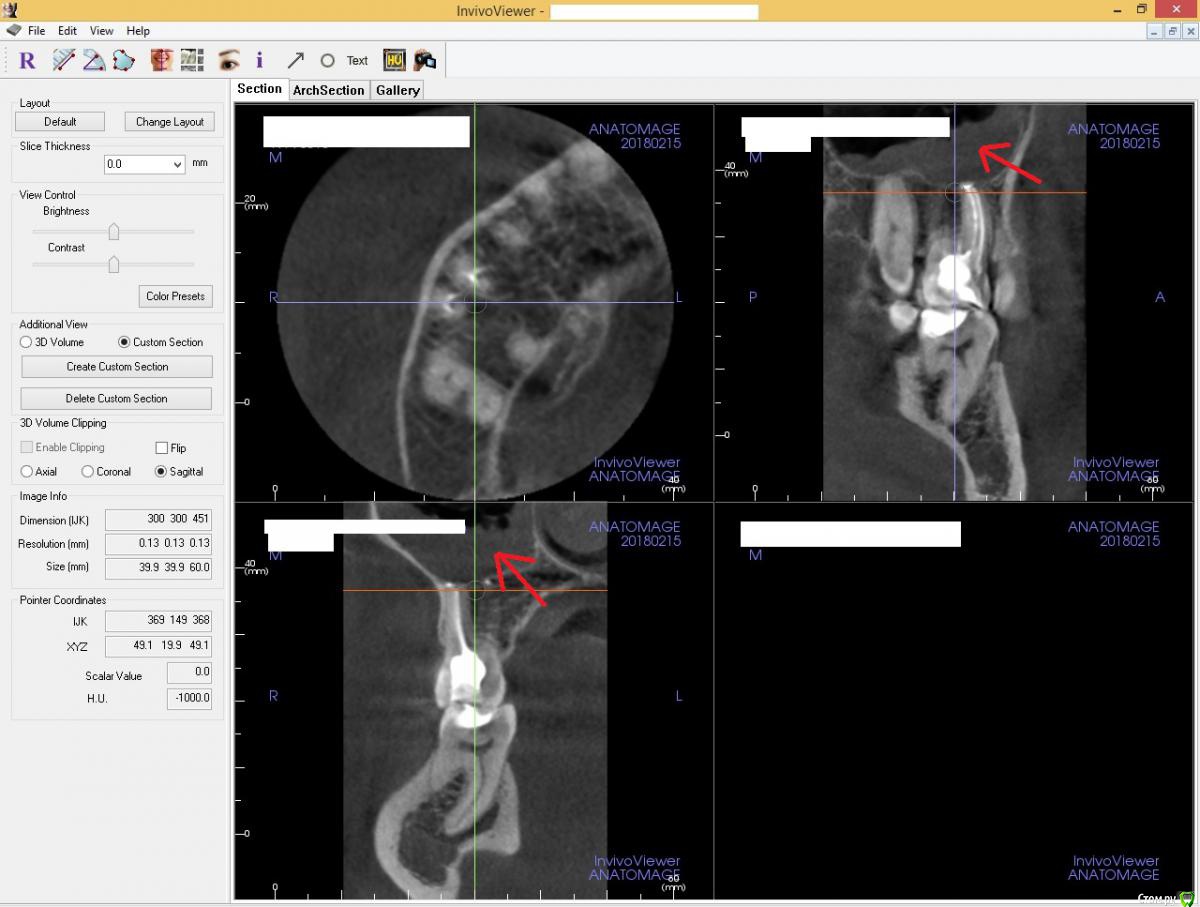

usilitel Опубликовано 21 ноября, 2018 Автор Поделиться Опубликовано 21 ноября, 2018 (изменено) Само в организме ничего не проходит, тем более воспаление в пазухе!Тогда как объяснить это:?Разница между 1-ым и 2-ым снимками = 2 недели, на 2-ом воспаление прошло. Никакого лечения в этот период не было, даже таблетки не пил. 1-ый снимок сделан через 3 дня после депульпации зуба.Может слизистая "умерла"? Типа некроз слизистой гайморовой пазухи. Такое бывает вообще? Изменено 21 ноября, 2018 пользователем usilitel Ссылка на комментарий